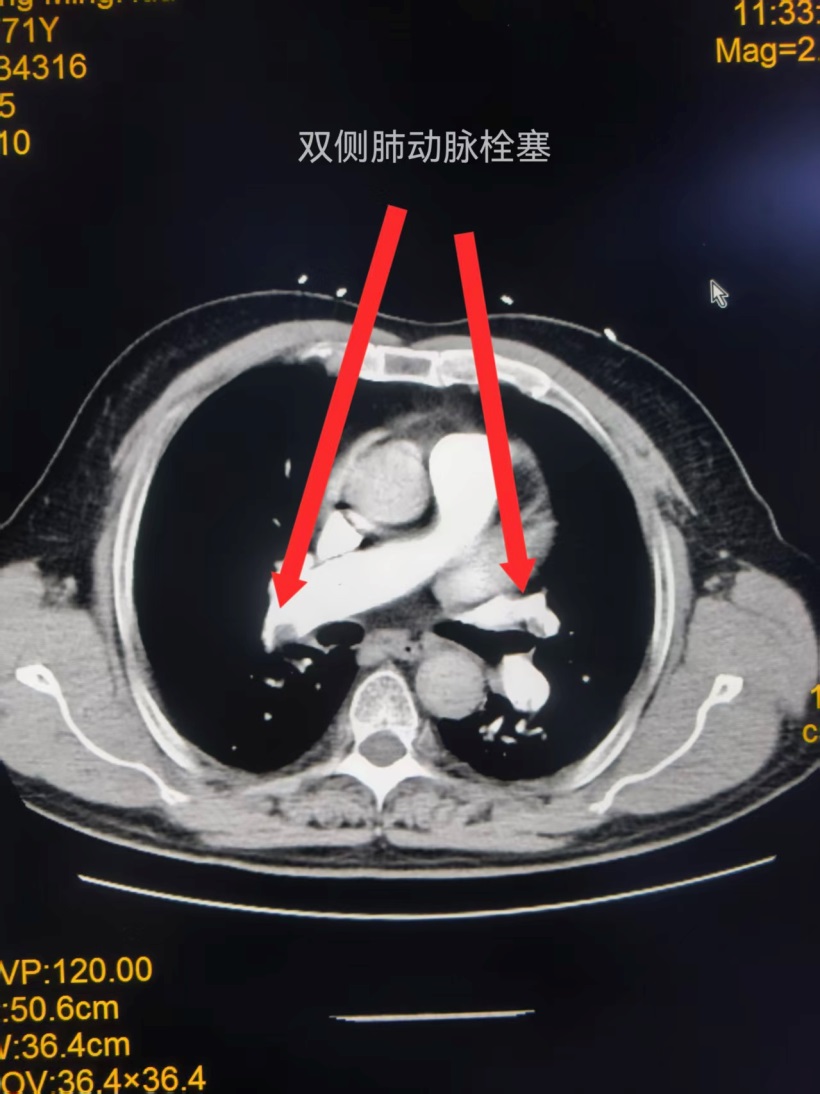

患者为71岁男性,因头晕、胸闷十余天入院治疗。入院后完善相关检查,提示D-二聚体升高,血气分析显示低氧血症、低碳酸血症,经CTPA检查后确诊为双肺肺栓塞。肺栓塞发病急、病情凶险,随时可能危及生命,玉林市红十字会医院心血管内科二区介入团队第一时间评估患者病情,快速制定个性化手术方案。

手术在介入导管室进行,医护团队配合有条不紊。医生进行右股静脉穿刺、置入鞘管及造影导管操作时,护理人员精准完成给药、器械传递等配合工作,保障手术流程顺畅推进。术中造影清晰显示,患者右肺主干、右上肺及左肺动脉存在多发血栓,且手术中患者突发心率骤降至30次/分,病情再度告急。